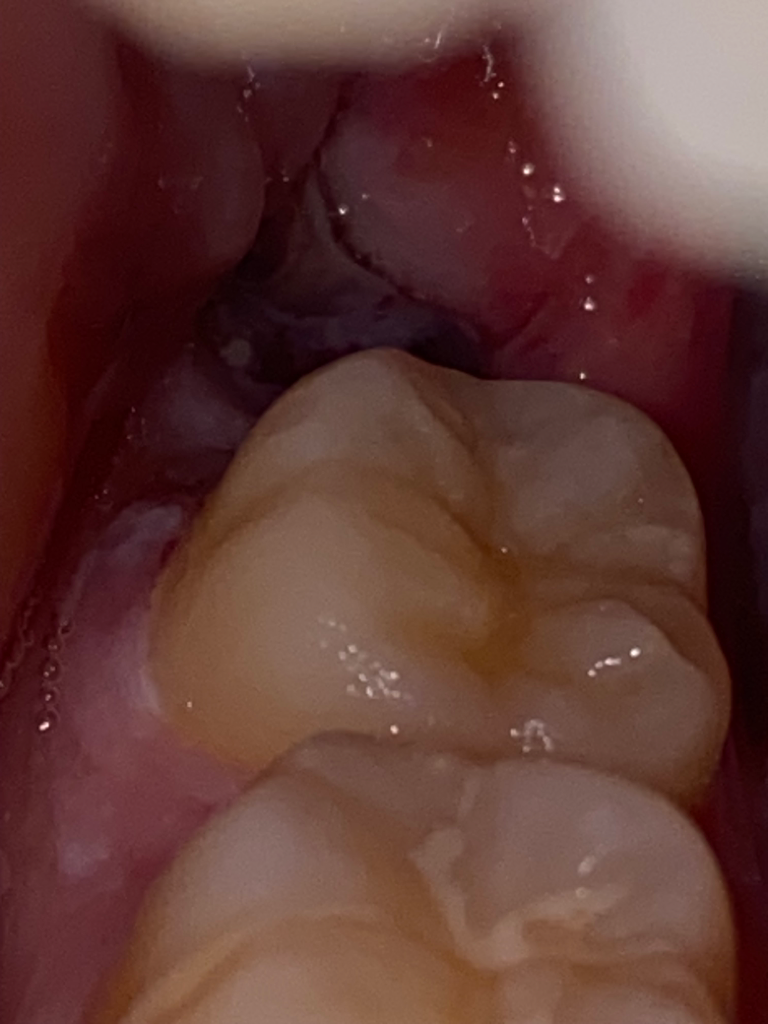

드라이 소켓인지 구분 해주실 수 있나요 ㅠㅠㅠㅠㅠㅠ

발치 4일차 양치하다 혈병이 떨어진거같은데 당일 빨대를 사용했어서 드라이소켓일까 불안해요 ㅠㅠ

단순발치였고 실밥도 꼬매지않았어요

이 사진은 2-3일차 사진입니다

떨어진 후 사진이에요 ㅠㅠ!

드라이소켓은 감염의 일종으로 통증도 심하고 냄새도 엄청나게 납니다. 사진상으로는 크게 문제가 없는거 같으니 너무 걱정하지 않으셔도 될것같습니다.

드라이소켓은 증상이 심한 통증과 악취가 납니다. 사진상으로도 크게 문제가 될 것은 안보입니다.

드라이 소켓은 발치후 24~48시간 사이에 갑자기 발생합니다..혈병은 적당한 시기에 탈락한것 같고 드라이소켓은 아닌것 같습니다.